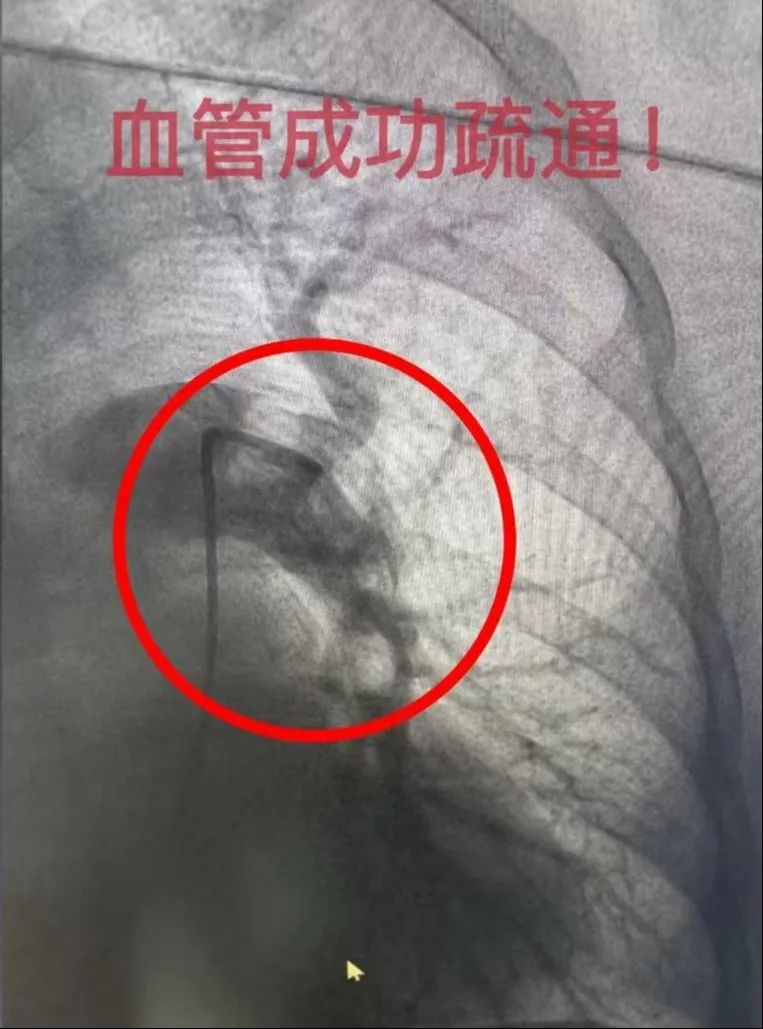

无影灯下,一根细若铅笔芯的导管从患者大腿根部进入血管,在X光的引导下精准抵达栓塞部位,再用微型器械将顽固血栓粉碎,最后通过导管精准喷洒溶栓药物。随着血液逐渐流动,血氧值变得平稳,患者的生命体征终于稳定下来。

这种"血管清道夫"微创技术,采用"先拦截后清除"的策略,避免了传统溶栓导致血栓脱落的风险,同时能针对大块血栓进行精准粉碎和溶解